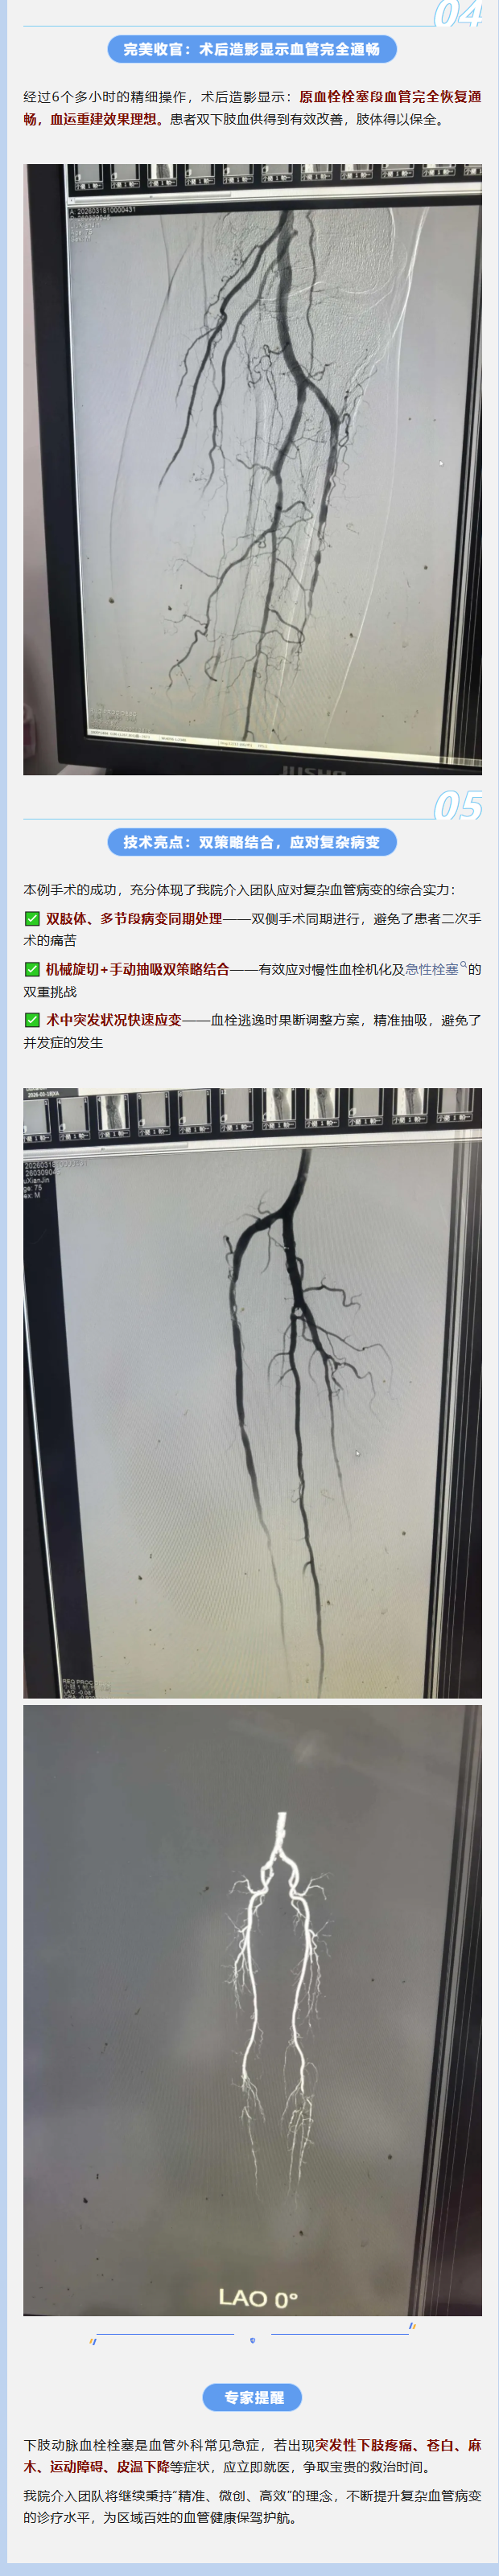

患者为75岁男性,因双下肢缺血症状来院就诊。经血管造影检查发现,患者双下肢动脉存在严重血栓栓塞:右侧累及腘动脉-胫腓干,左侧累及胫腓干。由于病程处于亚急性-慢性期,血栓已部分机化,质地坚韧、附着牢固,大大增加了手术难度。

手术的关键步骤是清除血栓、恢复血流通畅。团队首先使用Straub-Rotarex导管进行机械性旋切,成功清除大部分血栓主体。

然而,在旋切过程中,部分血栓碎片意外逃逸至远端更细血管——这是介入手术中最为棘手的突发状况之一,若处理不当,可能导致“垃圾脚”综合征,进一步加重肢体缺血。

术中即时调整方案! 团队果断改用6F血栓抽吸导管,对逃逸血栓进行精准抽吸,成功清除了远端血管内的碎片,避免了肢体缺血加重的风险。

随后,针对潜在的动脉硬化狭窄病变,团队使用球囊导管进行扩张成形,顺利恢复了流出道的血流通畅。